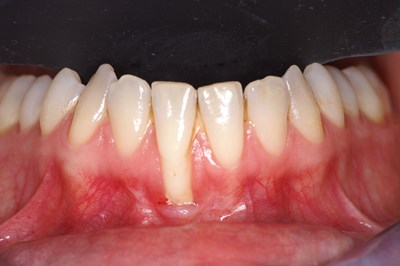

Recessiebedekking (terugtrekkend tandvlees)

Terugtrekkend tandvlees

Er is sprake van recessie op het moment dat het tandvlees teruggetrokken is en de tandwortel zichtbaar is. Recessie kan ontstaan door afwijkend poetsgedrag, (te hard poetsen, waardoor schade aan het tandvlees ontstaat), afwijkende stand van een tand of na een beugelbehandeling. Deze vorm van terugtrekkend tandvlees is over het algemeen goed te behandelen. Indien de recessie is ontstaan door een tandvleesontsteking, is hier in de meeste gevallen weinig meer aan te doen.

Behandeling van een behandelbare recessie zal zich in eerste instantie richten op het aanpakken van de oorzaak van de terugtrekking (aanpassen poetsgedrag). Daarna kan eventueel middels een chirurgische behandeling de recessie weer met tandvlees bedekt worden.

Praktijkvoorbeelden:

Voor behandeling                                                                    Na behandeling